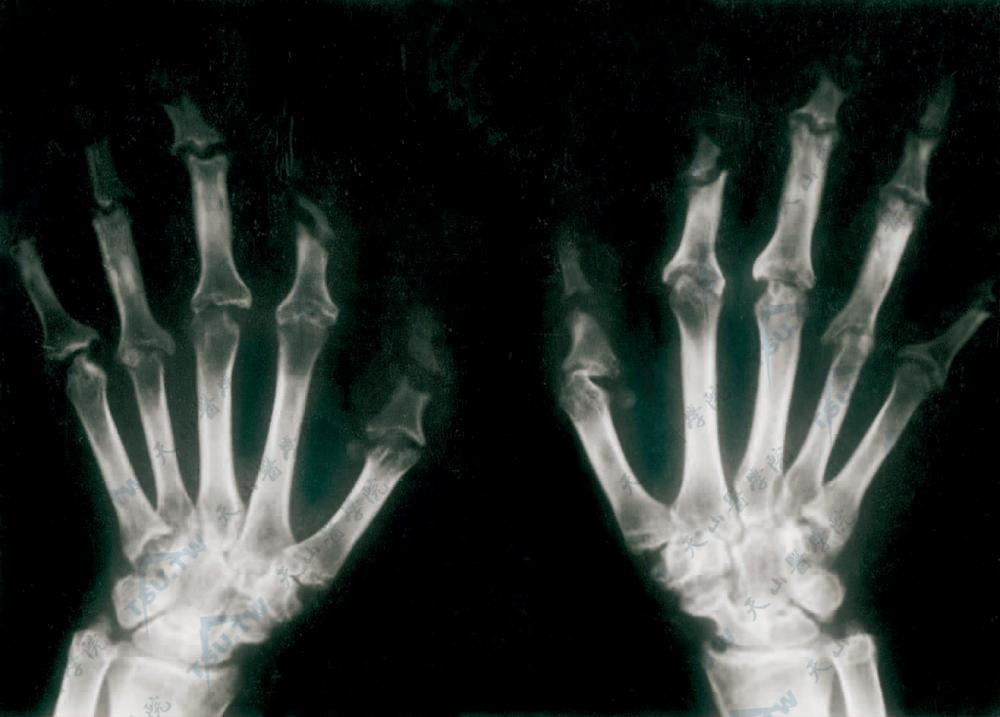

多中心网状组织细胞增生症症状:双手指掌指骨近端骨质破坏,缺损